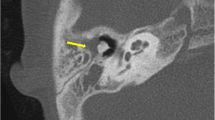

Fifty-five-year-old male with long-standing left-sided deafness, now presenting with a sudden onset of facial nerve paralysis. Supralabyrinthine (Class I) congenital petrous bone cholesteatoma (CPBC) in the left temporal bone. Coronal (a) and axial (b) computed tomography (CT) images of the left temporal bone show a well-circumscribed lytic lesion in the supralabyrinthine region with involvement of the geniculate ganglion (arrowhead in a), posterior extension medial to the vestibulum and dehiscent internal auditory canal (IAC) (arrow in b). There is high signal intensity in the medial petrous bone on EP DWI (b1000) (c) partially corresponding to the known cholesteatoma (arrow in c). There is a distorted aspect of the cholesteatoma making it less conspicuous. EP DWI is more susceptible to artifacts, mainly between the temporal bone and brain tissue (arrowhead in c), and has a lower in-plane resolution compared to non-EPI (compared to the DWI in Fig. 6)